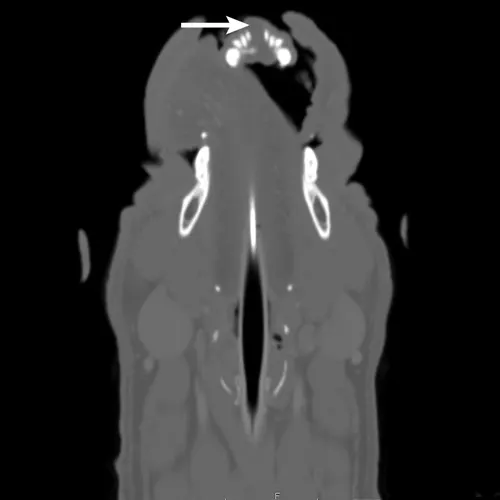

Figure 3

Sagittal CT image of the head showing an oral mass (arrow) of the rostral mandible

CBC and serum chemistry profile were within normal limits. Three-view thoracic radiographs were negative for metastatic disease. The patient was anesthetized, and CT of the head and thorax and an incisional biopsy were pursued in the same anesthetic period. The CT scan showed a well-defined, 2.2 x 2.5 x 1.4-cm noncontrast-enhancing, soft-tissue–attenuating mass on the rostral dorsal aspect of the mandible at the level of the incisor teeth, with mild lysis of the mandible and widening of the interdental space at the mandibular symphysis (Figures 2 and 3). The mandibular and retropharyngeal lymph nodes (the most important lymphatic centers for a tumor in this region) and other lymph nodes of the head and neck appeared normal.